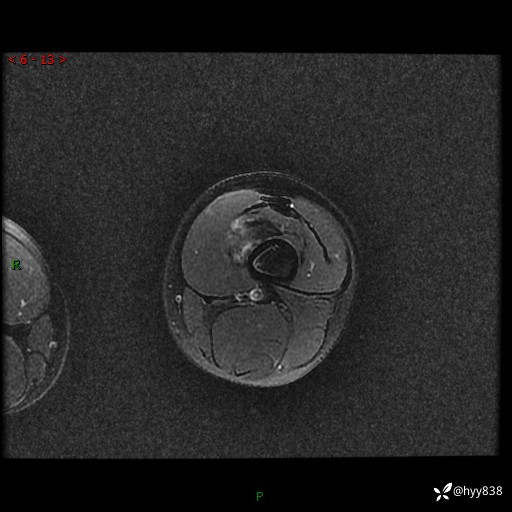

左大腿MRI平扫+增强